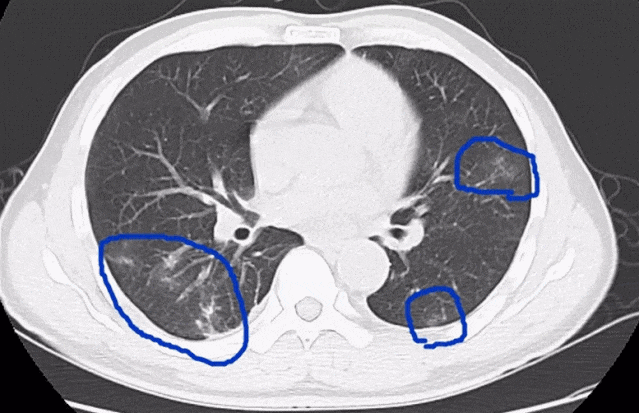

2020年9月,深圳的一家三口在品尝“醉蟹”后,先后出现发热、腹痛、腹胀、乏力、食欲下降、干咳等症状。经检查,他们均患上了“肺吸虫病”。

图源:深圳卫健委